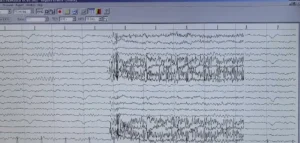

Obiettivi: L’emicrania cronica (CM) è caratterizzata da dolore ricorrente alla testa, spesso associato ad alterazioni elettroencefalografiche (EEG) e ad asimmetrie nella circolazione venosa intracranica. È considerata uno dei sintomi della insufficienza venosa cerebrospinale cronica (CCSVI).

Metodi: Sette pazienti con diagnosi di CCSVI ed emicrania cronica, con o senza altri sintomi, sono stati sottoposti a angioplastica transluminale percutanea (PTA) delle vene giugulari interne. Tutti hanno eseguito risonanza magnetica venografica e/o ecocolordoppler prima della PTA, sette EEG preoperatori e cinque EEG di controllo post-PTA. L’intensità del dolore è stata valutata con una scala numerica prima e dopo l’intervento.

Risultati: Tutti i pazienti hanno mostrato un miglioramento del flusso ematico giugulare dopo PTA. In cinque pazienti su sette è stato osservato un miglioramento del ritmo alfa cerebrale all’EEG post-operatorio e tutti hanno riportato una significativa riduzione del dolore.

Conclusioni: Queste osservazioni preliminari suggeriscono una stretta associazione tra emicrania cronica, anomalie venose intra- ed extracraniche e alterazioni EEG, e indicano la venoplastica come possibile approccio terapeutico da approfondire.

Leggi di Più..Lettura del Tracciato EEG –

La procedura di acquisizione EEG evidenzia come la corretta gestione...